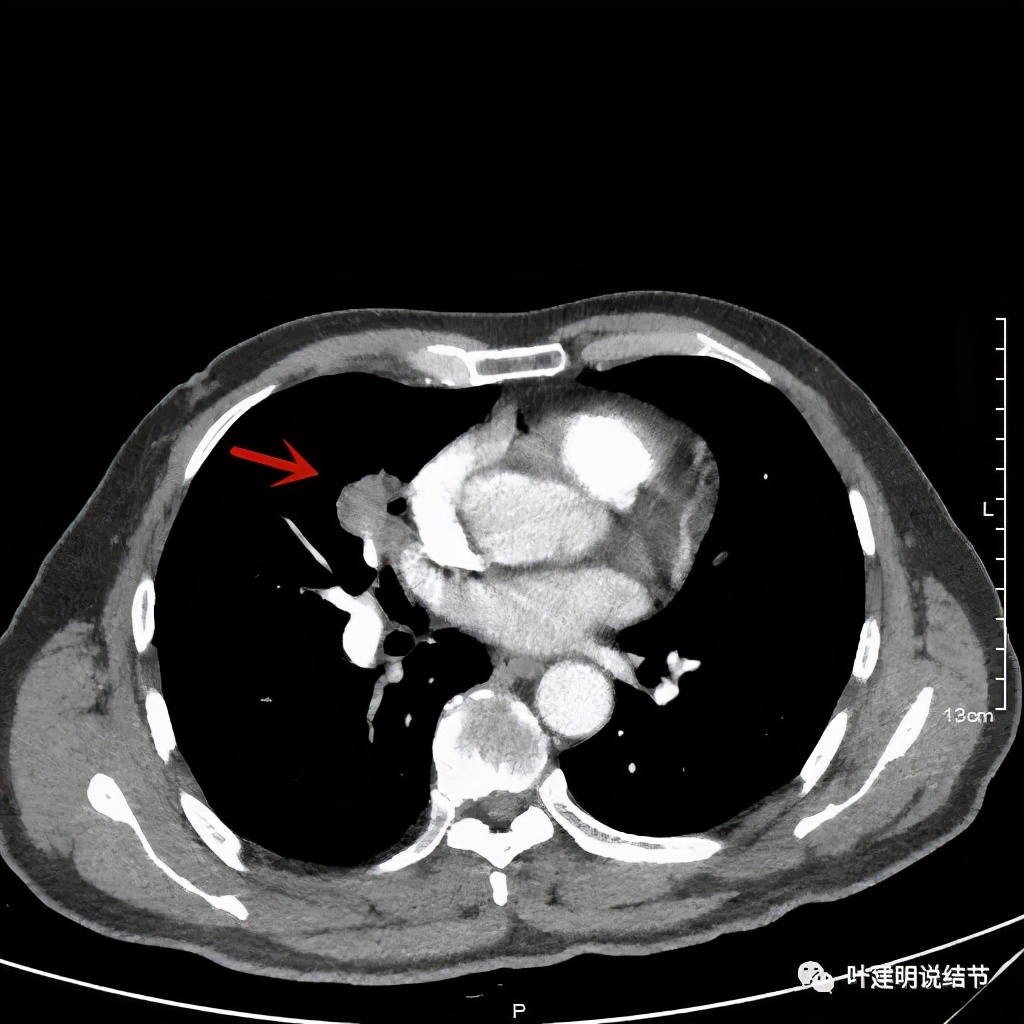

那么当时的胸部影像又是如何的呢?

病灶有分叶及胸膜牵拉

以上几图示病灶膨胀感明显,无卫星灶,周围无渗出性改变